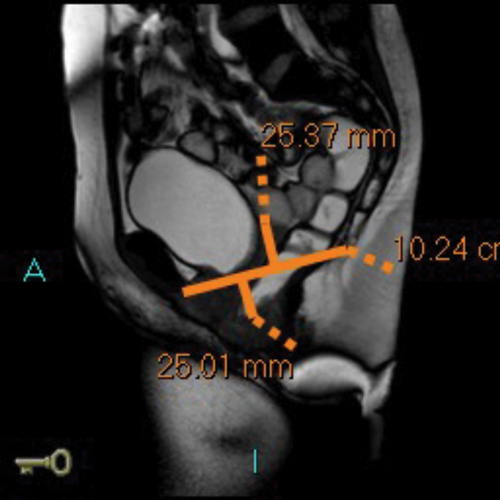

After an initial digital rectal examination, 120mls of ultrasound jelly is instilled into the rectum via a rectal tube with the patient in the left lateral position. The patient is then turned to lie supine and positioned so that the top of the Sense-body coil is at same level with the iliac crest. The MRI scan protocol includes T2 axial and coronal sequences and sagittal ‘cines’ squeeze, bear down and two defecatory attempts with a couple of minutes rest in between. In cases of incomplete evacuation, a repeat evacuation may be needed or a coronal cine.

In addition the anterior and middle compartment is assessed, particularly for the presence and anatomy of a cystocoele or vault prolapse. The T2 sequences also allow pelvic evaluation for other incidental pathologies (Figure 2).

Figure 2a: Baseline MR proctogram.

Figure 2b: Pelvic floor descent MR proctogram.